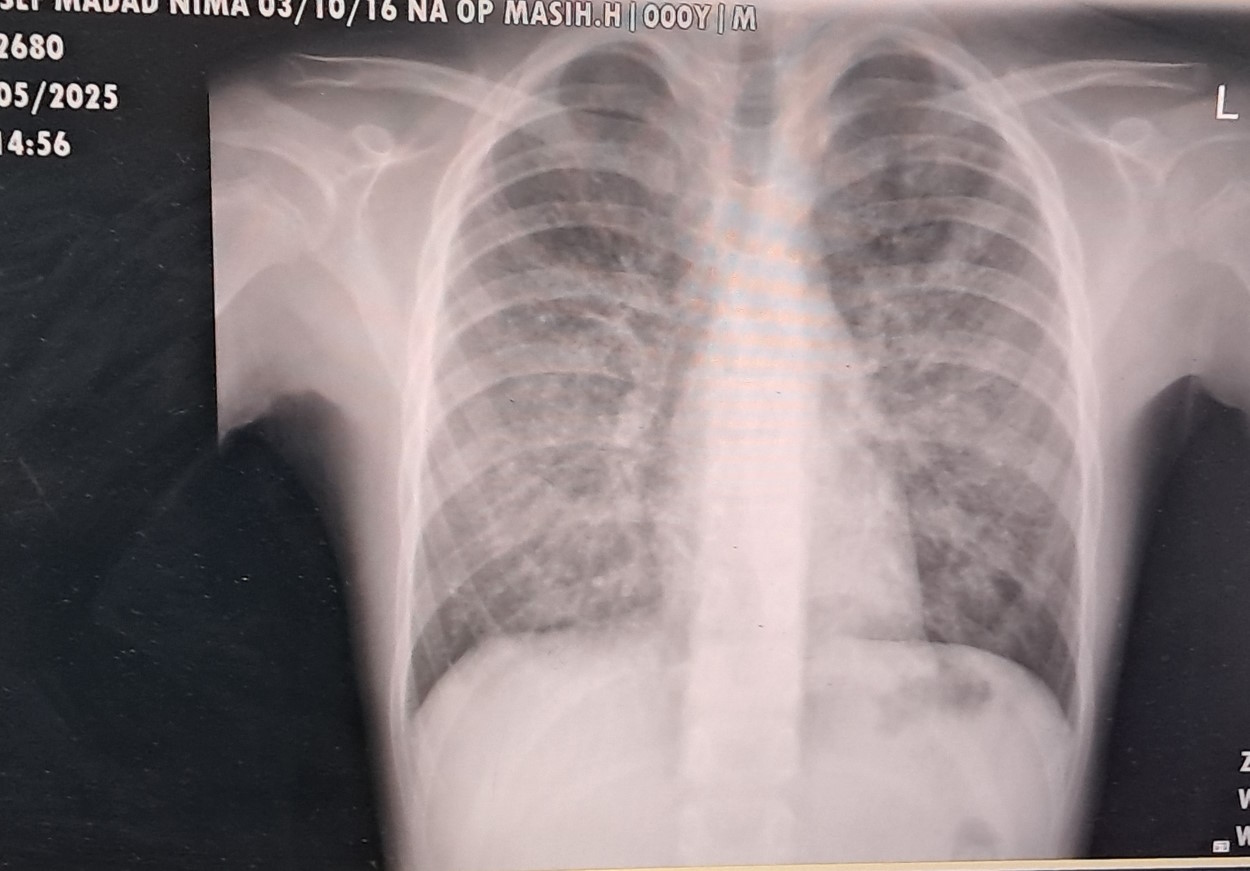

مانند دیگر بیماری های ریوی شدید ابتدا بیمار توسط متخصص ریه ویزیت می شود و از بیمار عکس ساده ریه و سپس سی تی اسکن گرفته می شود. در صورت تایید متخصص ریه بیمار برای انجام بیوپسی بافت ریه به جراح یا برونکوسکوپیست ارجاع داده می شود؛ در نتیجه، تشخیص قطعی بیمار توسط پاتولوژیست (بافت شناس) باید تأیید شده باشد.